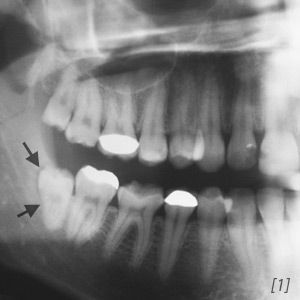

Bild 1: Das Röntgenbild lässt die knöcherne Veränderung des Kieferknochens durch das Zahnsäckchen gut erkennen. Der Weisheitszahn 48 hat sich in den distalen Bereich des Kieferknochens geschoben.

Bleibt der Durchbruch des Weisheitszahnes als Folge von Platzmangel in dieser Phase stehen, werden Kieferknochen und die Schleimhaut teilweise von den Zellen des Zahnsäckchens umgebaut und es entstehen taschenförmige Ausbildungen. Es kommt im weiteren Verlauf zu sichelförmigen Umbauprozessen und einer Atrophie des Knochens, meistens in distaler Richtung (nach hinten).

Durch die Belastung und den Druck verfestigen sich die Kieferknochenzellen. Das Zahnsäckchen wird, durch die beim Zahndurchbruch entstandenen Entzündungen in der Mundschleimhaut, von den Zellen des Lymphsystems abgebaut.